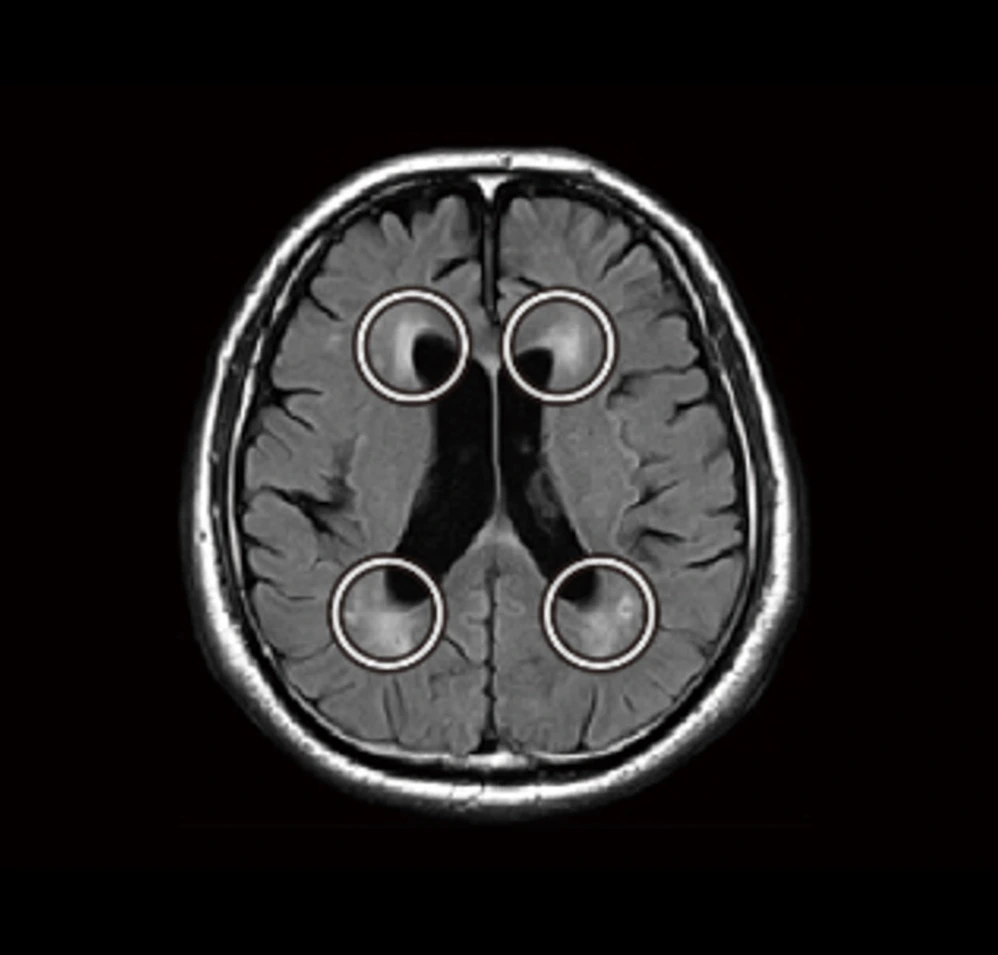

上の脳画像には白い斑点のようなエリアがあります。

これは白質病変と呼ばれ、脳の血管の健康度の目安になると考えられます。加齢とともに現れる変化ですが、急速な増加は、将来の認知症や脳梗塞のリスク因子と知られています。

脳血管のダメージに伴う脳梗塞や血管性認知症の兆候である白質病変体積の変化を未病の段階から微細な兆候を捉えることができます。

| FLAIR | 脳溝や脳室に接する病変の診断に有用 |